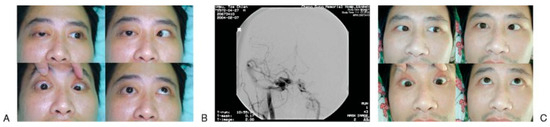

Treatment of the syndrome depends on the cause, if it can be ascertained. Patients present chemosis, pulsating exophthalmos, orbital or frontal bruit, and deterioration of vision in addition to clinical finding compatible with SOFS; traumatic CCSF [26,32] should be highly suspected as a cause of SOFS. Prompt carotid angiography is conducted to confirm CCSF, which can be successfully embolized with detachable balloon or coils [32,33]. The symptoms of ptosis, facial numbness, and ophthalmo- plegia usually resolved progressively within few months after embolization (Figure 4).

Figure 4.

A 32-year-old male with traumatic superior orbital fissure syndrome (SOFS) caused by carotid-cavernous sinus fistula (CCSF). (A) Patient presented the symptoms of SOFS along with orbit bruit. (B) Anterior-posterior right carotid angiogram showing a large CCSF. (C) One month after embolization, the eye movements are almost back to normal, except the abducens nerve.